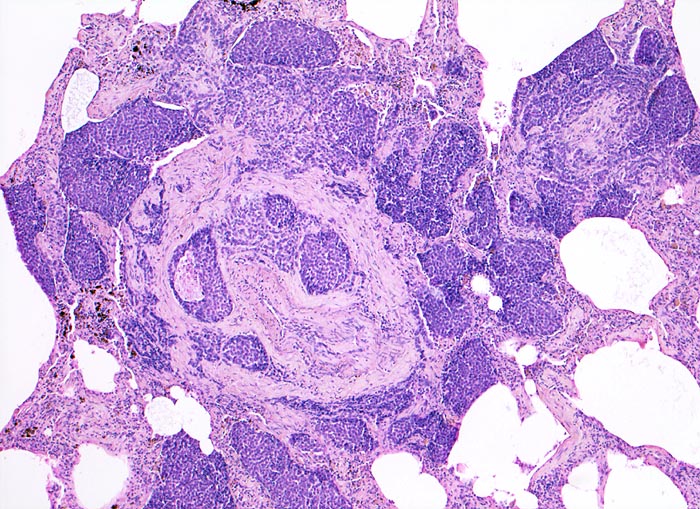

PathoPic – image database / PathoPic ID 4731 - Lymphangiosis carcinomatosa

Lymphangiosis carcinomatosa

Lunge

Dunkle solide Tumorinfiltrate gruppieren sich um einen zentralen Pulmonalarterienast. Der Tumor liegt aber nicht nur innerhalb präformierter Gefässräume, sondern bildet invasive unscharf begrenzte Herde im perivaskulären Bindegewebe und füllt die angrenzenden Alveolen aus. Ablagerungen von schwarzem Anthrakosepigment.

Metastasierendes Tumorleiden bei unbekanntem Primärtumor. Autoptisch primäres peripheres neuroendokrines Karzinom der Lunge mit ausgedehnter lymphogener und hämatogener Metastasierung.

Obwohl keine sichere Lymphgefässwand identifiziert werden kann, ist aufgrund der Lage eines Teils der Tumorzellaggregate rund um einen Pulmonalarterienast und der scharfen Begrenzung anzunehmen, dass sich der Tumor in den dort lokalisierten Lymhspalten ausbreitet.